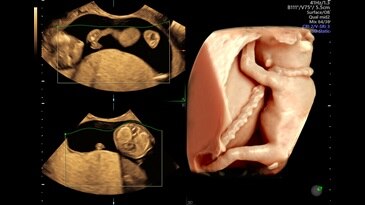

· 初期胎児精密超音波 妊娠初期(11週4日から13週6日まで)に胎児・絨毛・臍帯・羊水をできる限り詳しく観察し、大きな形態異常などを見つけます。niptを受けられた方にもおすすめします。 ご希望により、nt、鼻骨、静脈管波形、三尖弁、心拍数の超音波マーカーを用いて、21トリソミー · 我が子には、胎児の発育が鈍化してしまう「胎児発育不全」の症状が現れていました。 原因は多種多様ですが、主に下記と言われています。 1胎児の病気や先天異常 胎児に何らかの病気や先天的な原因があり、妊娠初期から順調に育たない場合があります。赤ちゃんが小さい原因のひとつ · 妊娠の症状が出てこなくても心配せず、ラッキーだと思って妊娠期間を過ごしていきましょう! 妊娠6週目 ママのやること・気をつけること 妊娠中のママが気づく妊娠初期症状の1つは、おっぱいが大きくなること。これ以外に妊娠ホルモンの増加によって

超音波画像